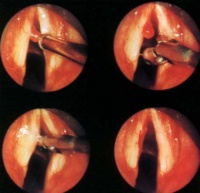

喉镜检查可见一侧声带前、中1/3附近有半透明、淡黄白色或粉红色的肿物,位于声带边缘、声带边缘上或声门下,表面光滑,可带蒂、也可广基,带蒂的息肉有时随呼吸上下运动。弥漫性声带息肉病则出现整个声带弥漫性息肉样变,两侧声带膜部边缘有水肿样肿块,大的可悬垂于声门下,可堵塞声门前部

2、喉镜检查:声带息肉多一侧呈灰白色或淡红色光滑的赘生物,有蒂或广基或弥漫性声带边缘呈灰白腊肠状肿块。

较大或已纤维化的声带小结和长期声带息肉患者,经过声带休息、发声训练和药物治疗无效时,应采取手术的方法进行治疗。目前,患者可采用的手术方法主要有:①在局部麻醉下通过间接喉镜将声带小结或声带息肉切除;②在光导纤维喉镜下运用等离子将声带小结或声带息肉去除。由于早期的声带癌和有些声带息肉用肉眼难以鉴别。因此,对切除的声带息肉应作相应的病理检查。对在局部麻醉下不能配合治疗的患者,应采取全身麻醉的方法对其进行手术治疗。③支撑喉镜下切除术。手术要注意如果双侧声带前部粘膜不能同时损伤,否则可造成声带粘连。 术后应禁烟,纠正不良的发音习惯,否则易复发。

答:声带息肉常见于声带前中1/3。如息肉小,而且又不在声带边缘上,一般无明显症状。如有声音嘶哑,说明息肉较大,已妨碍声带的闭合,此时一般都需手术摘除声带息肉。手术方法一般有三种:间接喉镜下手术、直接喉镜下手术、喉显微手术。由医师视情况采用何种手术方法。术后应禁止讲话3~7天。如手术医师经验丰富,操作良好,一般不会有什么后遗症,更不会导致变哑。